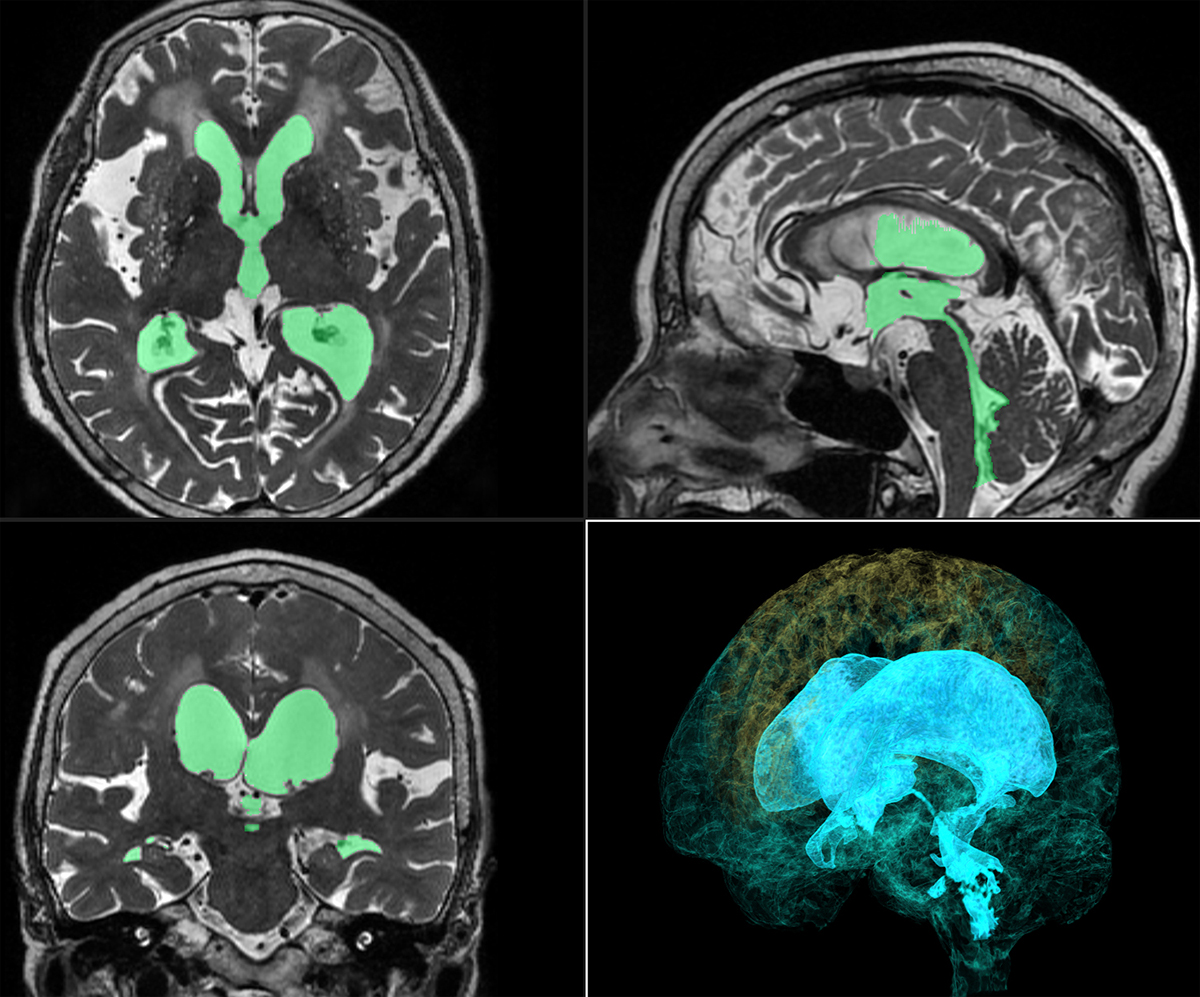

水頭症のひと 脳神経外科の病気:水頭症 | 病気の治療 | 徳洲会グループの詳細情報

脳神経外科の病気:水頭症 | 病気の治療 | 徳洲会グループ。特発性正常圧水頭症(とくはつせいせいじょうあつすいとうしょう。診断と検査|高齢者の水頭症 iNPH.jp。iNPHとは?|高齢者の水頭症 iNPH.jp。絵画の種類...油彩画・油絵形式...掛け軸・掛軸主題...人物・肖像壁掛けアート贄田越郎画主な画材...油彩絵の具